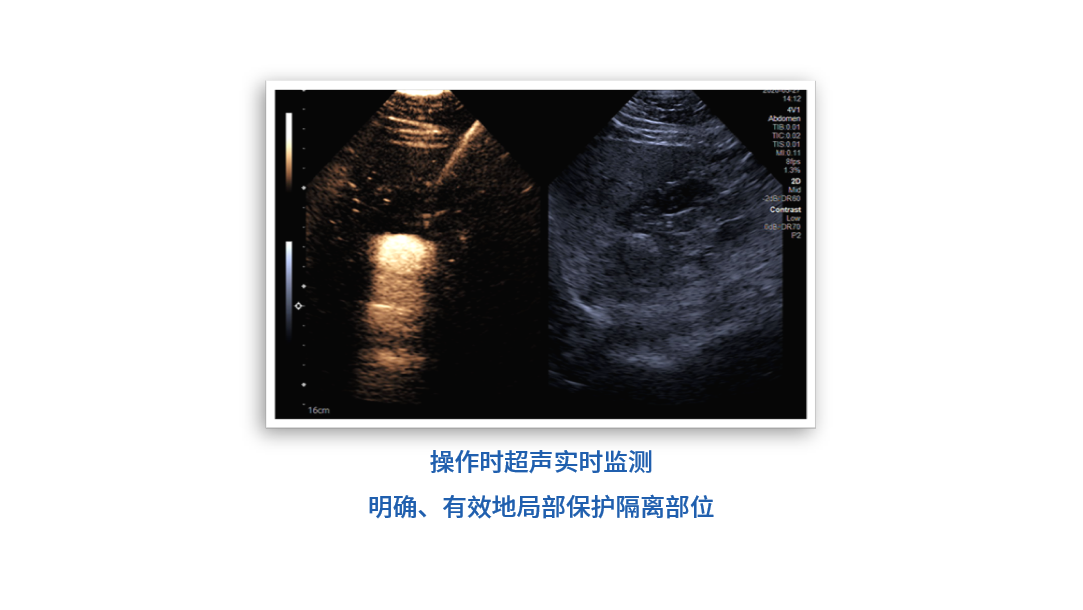

耀月? 微波治療球囊導(dǎo)管

• 球囊囊體兩端配有特殊雕刻顯影標(biāo)記,影像下定位更清晰

• 球囊在微波消融治療時間內(nèi)耐受高溫,具有良好的安全性和穩(wěn)定性